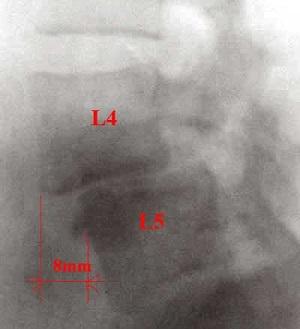

Для подтверждения диагноза спондилолистеза специалист назначает рентгенографию в прямой и боковой проекциях, что даёт возможность оценить степень деформации, угол и величину смещения.

Если есть подозрения на повреждение околопозвоночных структур, нервных корешков или спинного мозга, врач направляет на МРТ и КТ.